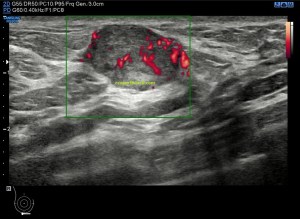

El protocolo es el típico, cortes en eje corto y largo, con doppler, para comprobar vascularización, como línea roja del lipoma. Imágenes 3,4 y 6.

La lesión era ovalada, hiperecogénica, ocupaba gran parte del músculo, pero respetaba parte de este, que era hipoecogénico (imagen 5), recuerda que así es por definición y que ésta ecogenicidad del músculo es referencia para el resto de ecogenicidades del aparato locomotor. Como te he contado, no había doppler color ni en modo angio.